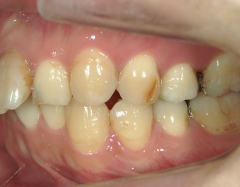

no.24_8228_治療前_右.jpgno.24_8228_治療前_正面.jpgno.24_8228_治療前_左.jpg